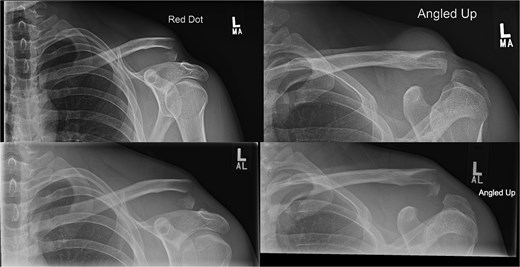

(A, B) Radiographs showing healing of the third case and radiological union at 6 weeks and 3 months post-operatively. (C–D) Radiographs showing complete healing of the third case and union at 6 months and 12 months post-operatively.

A 27-year-old male suffered a right lateral clavicle fracture after a fall (Fig. 5). He underwent TightRope fixation with stabilization of the coracoclavicular ligament. Rehabilitation was initiated early, and by three months, he had full shoulder motion and returned to overhead sports. Radiographs confirmed union, and the patient reported minor scar sensitivity and transient keloid formation, with no functional limitations (Fig. 6A–D).